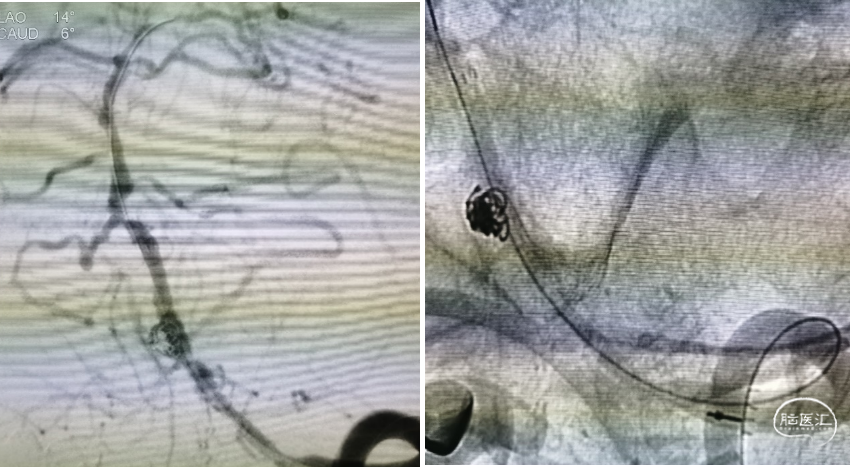

栓塞结束后造影情况,可见支架贴壁良好,血管狭窄较前改善,动脉瘤近全栓塞,远端大脑后动脉显影明显改善

术后DWI提示左侧小脑半球点状小梗死灶,患者无新增神经功能障碍,术后第三天出院